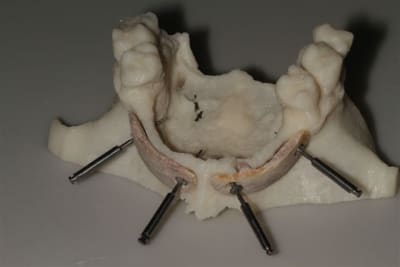

La première diapo est un essai pour justifier le concept (os non destiné à une utilisation greffe)

la deuxième est "tapée" dans une tête de femur de mauvais qualité (rejetée)

la troisième et suivante ce sont "les greffons" définitifs.